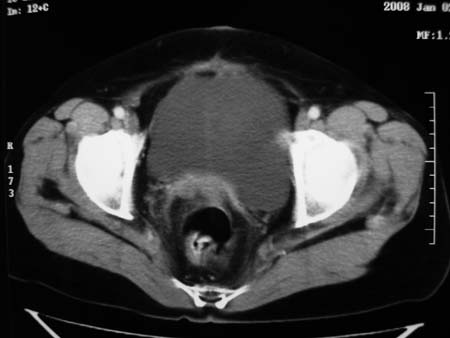

以下是引用卜一在2008-1-2 20:39:00的发言:[br]右侧附件区囊实性肿块,与膀胱壁分界不清,增强后实性部分显示强化。考虑为:右侧卵巢囊腺癌可能性大。支持!

以下是引用zhengfaming在2008-1-2 19:28:00的发言:[br]右下腹腔内附件区可见一囊实性混合密度块影,先考虑囊腺癌